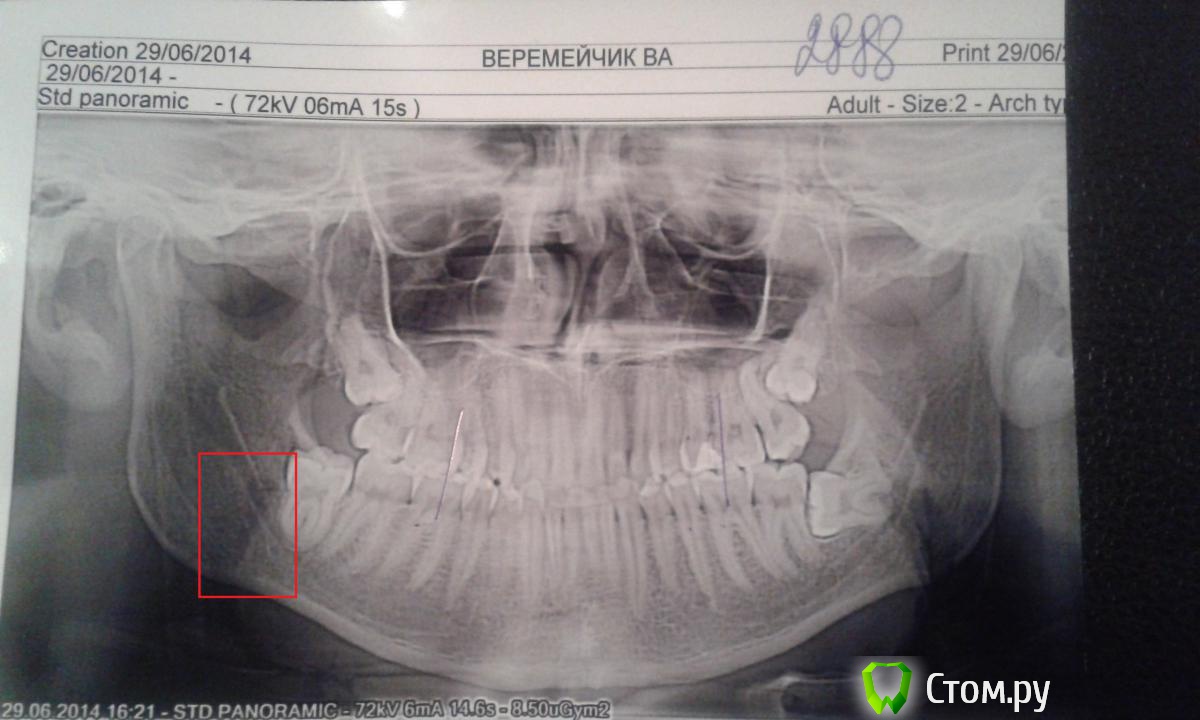

Василь Опубликовано 30 июня, 2014 Поделиться Опубликовано 30 июня, 2014 (изменено) Здравствуйте! Заранее спасибо за помощь, вот в больнице сказали что у меня трещина (то есть перелом без смещения), правда при этом единственное что мне было больно делать это двигать челюсть в сторону, больше боли не было, ну еще жевать не очень просто было, доктор сделал шинирование по Айви, прописал ибупрофен, и антибиотик 3 раза в день.Все правильно? (трещина с правой стороны) http://i062.radikal.ru/1406/e4/c062d17c6e6b.jpg (фото) Изменено 30 июня, 2014 пользователем Василь Ссылка на комментарий

dr-krasnov Опубликовано 30 июня, 2014 Поделиться Опубликовано 30 июня, 2014 Я бы по этой картнинке не рискнул говорить о переломе. Цифровой файл был бы намного информативнее. 3 Ссылка на комментарий

Bier Опубликовано 30 июня, 2014 Поделиться Опубликовано 30 июня, 2014 Перелом есть, лечение адекватное Ссылка на комментарий

Василь Опубликовано 30 июня, 2014 Автор Поделиться Опубликовано 30 июня, 2014 Я бы по этой картнинке не рискнул говорить о переломе. Цифровой файл был бы намного информативнее. Просто на руки мне только его дали. По нему вобще ничего не видно? Ссылка на комментарий

dr-krasnov Опубликовано 30 июня, 2014 Поделиться Опубликовано 30 июня, 2014 Ну покажите мне линию перелома коллеги . . . Ссылка на комментарий

Bier Опубликовано 30 июня, 2014 Поделиться Опубликовано 30 июня, 2014 Ну покажите мне линию перелома коллеги . . .сейчас порисовать негде, попробую так объяснить: пациент неверно расположил снимок, правая сторона на снимке справа, там горизонтально расположенный 48й зуб, от его медиального корня вниз, медиальнее от угла челюсти идет линия перелома. Ссылка на комментарий

DokDent Опубликовано 30 июня, 2014 Поделиться Опубликовано 30 июня, 2014 сейчас порисовать негде, попробую так объяснить: пациент неверно расположил снимок, правая сторона на снимке справа, там горизонтально расположенный 48й зуб, от его медиального корня вниз, медиальнее от угла челюсти идет линия перелома.Олег, не пойму: а надписи почему тогда читаются правильно? Если снимок наоборот, то и надписи вроде должны быть наоборот? Ссылка на комментарий

Bier Опубликовано 1 июля, 2014 Поделиться Опубликовано 1 июля, 2014 Олег, не пойму: а надписи почему тогда читаются правильно? Если снимок наоборот, то и надписи вроде должны быть наоборот?Вы правы, я ошибся. Но перелом там, где я написал 38 зуб надо будет потом удалить, месяца через 3-4, а то при удалении челюсть еще раз сломают ) 1 1 Ссылка на комментарий

DokDent Опубликовано 1 июля, 2014 Поделиться Опубликовано 1 июля, 2014 Вы правы, я ошибся. Но перелом там, где я написал Скорей всего Василий ошибся со стороной перелома Ссылка на комментарий

Korel Опубликовано 1 июля, 2014 Поделиться Опубликовано 1 июля, 2014 Если это считать переломом: http://s004.radikal.ru/i205/1407/59/80c987c0e7ab.jpg Я б на всякий пожарный сделал бы ещё один снимок. А то мало ли , вдруг боли от 38 ? 2 Ссылка на комментарий

kriokov Опубликовано 2 июля, 2014 Поделиться Опубликовано 2 июля, 2014 (изменено) топикстартеруВас боли, отек, боли при жевании с какой стороны беспокоят, справа?Иммобилизация челюсти в любом случае для Вас показана.Ну и снимки новые не повредят, как уже сказали Ну покажите мне линию перелома коллеги . . .то же не увидел. Сравнивал кортикальную канала, он вроде четко виден, нигде не прерывается, и не смещается. Изменено 2 июля, 2014 пользователем kriokov 1 Ссылка на комментарий

ПалСаныч Опубликовано 2 июля, 2014 Поделиться Опубликовано 2 июля, 2014 Я считаю что линия перелома в области 48 есть, она крива и прослеживается сверзу донизу ( видно по кортикалке), но я и с подозрениями Олега Юрьевича согласен, я б на область 38 обратил внимание тоже. В плане тактики ничего не изменится, а если станет вопрос о тяжести травмы и страховых выплахтах, то за двусторонний перелом дают больше))) Ссылка на комментарий